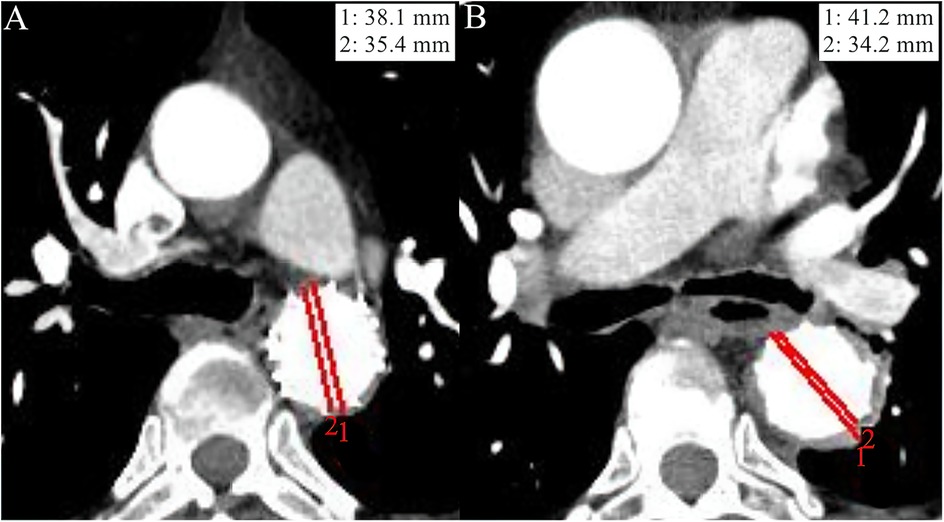

Objective: Thoracic endovascular aortic repair (TEVAR) is increasingly performed in patients with acute type B intramural hematoma (IMH). This study aimed to evaluate the effect of diabetes mellitus (DM) on postoperative clinical outcomes and aortic remodeling degree of acute type B IMH patients undergoing endovascular repair. Methods: We retrospectively identified patients diagnosed with acute type B IMH at two medical centers between January 2017 and January 2024. Study subjects were divided into DM and none DM (nDM) groups. Baseline characteristics, procedure details, and postoperative outcomes were extracted for further analysis. Results: Forty-four patients were included in the study and were divided into DM (n=12) and nDM groups (n=32). Preoperative demographic characteristics, laboratory biomarkers, and imaging data were similar between the two groups. Compared with nDM group, the DM group presented a slightly higher rate of patients without postoperative major adverse events (MAE) (75.0% vs 68.8%, p = 0.651). At the 1-year follow-up, the DM group exhibited a significantly higher degree of aortic remodeling, as assessed by the TAD/TLD ratio (total aortic diameter [TAD] divided by the true lumen diameter [TLD] at the maximal IMH thickness) (DM group: 1.09 ± 0.04; nDM group: 1.17 ± 0.10, p = 0.032). Cox multivariate regression revealed that a TAD/TLD ratio > 1.32 increased the incidence of postoperative MAE significantly. Conclusions: DM is positively associated with the prognosis of patients with acute type B IMH undergoing TEVAR and promotes postoperative aortic remodeling. Moreover, a TAD/TLD ratio > 1.32 independently predicts the incidence of